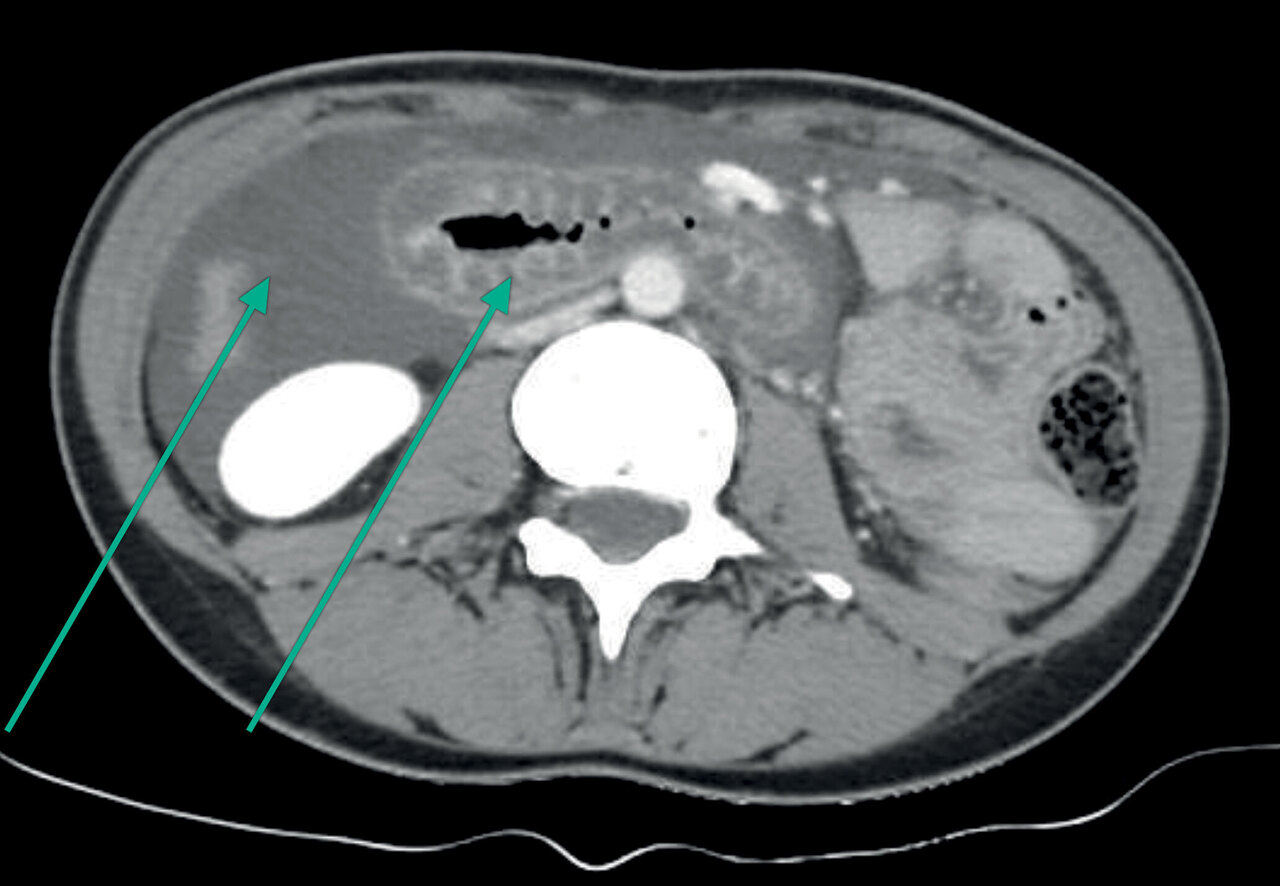

Une femme de 29 ans, sans antécédents, sous contraception orale depuis quelques mois, a des douleurs abdominales diffuses d’apparition brutale avec vomissements. Les analyses réalisées lors de la consultation aux urgences montrent des polynucléaires neutrophiles à 18 000/mm3 ; la protéine C réactive (CRP) est inférieure à 4 mg/L. Un scanner abdominal est réalisé.

L’angiœdème bradykinique est une maladie héréditaire avec le plus souvent un déficit en C1-inhibiteur, responsable de crises douloureuses abdominales (syndrome subocclusif ou ascite) et d’épisodes d’oedèmes de la face ou du larynx, qui en font toute la gravité.